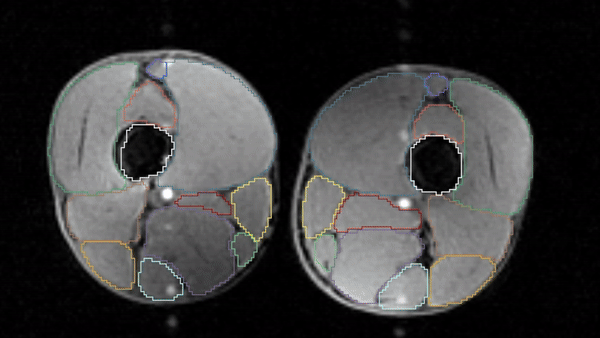

Precise Measurements

Springbok Analysis Types